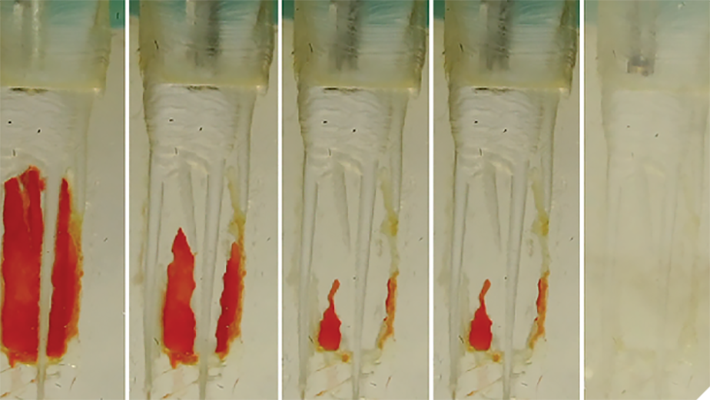

Deep Shape in Endodontics: Significance, Rationale and Benefit

The goal of endodontic treatment is to prevent or cure, when present, Lesions of Endodontic Origin, at times referred to as apical periodontitis. The role of bacteria in the pathogenesis of endodontic disease is well established, and therefore, it is critical to eradicate these pathogens by employing the highest level of presently developed standards. This … Read more